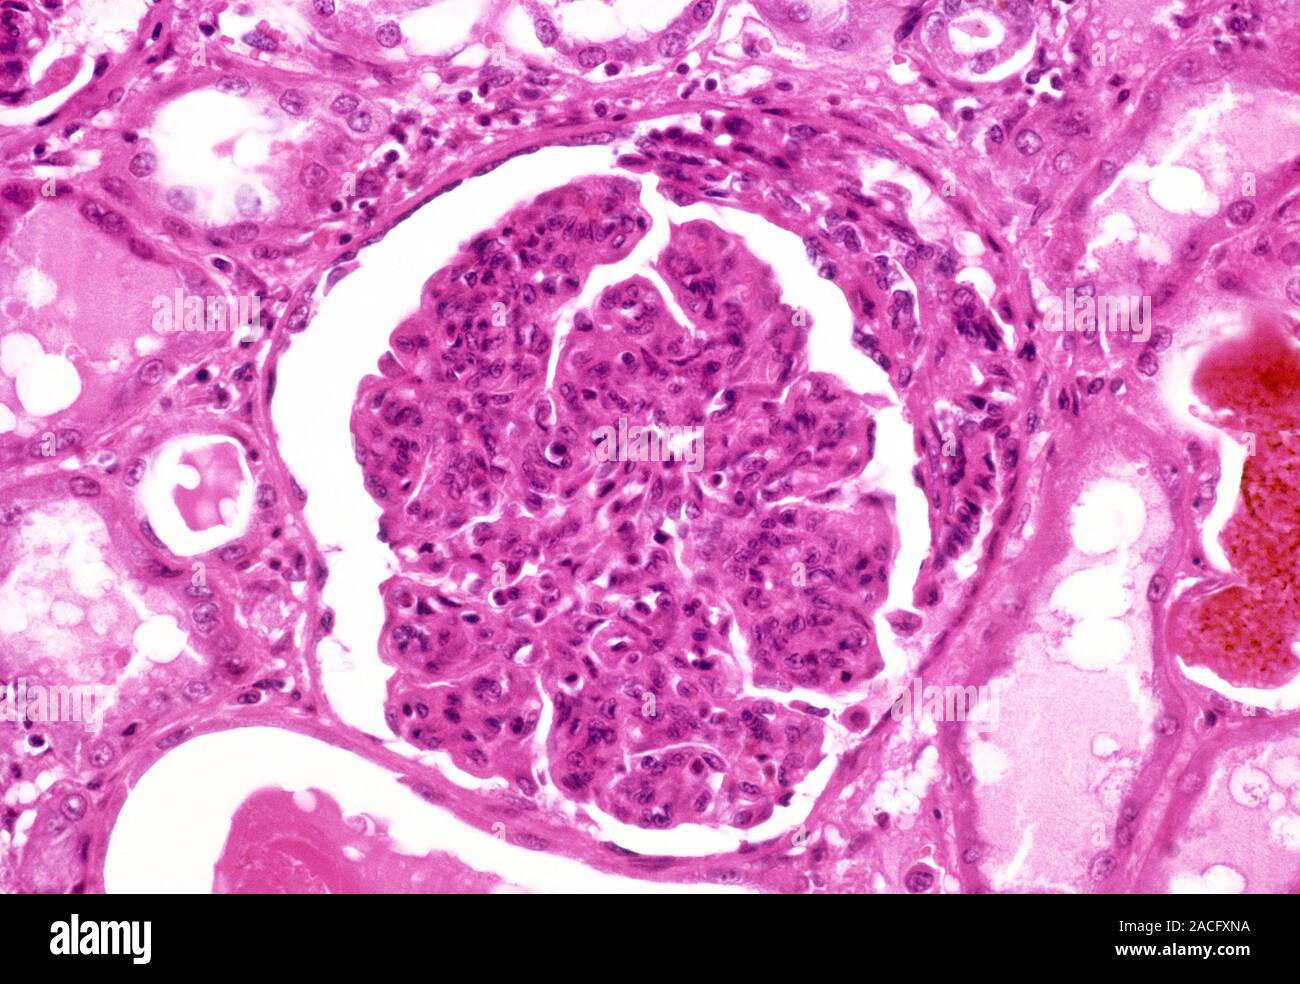

From www.alamy.com

Glomerulonephritis. Light micrograph of tissue from a kidney in a case Kidney Filter Inflammation (Glomerulonephritis) Glomerulonephritis happens when the kidneys' blood filters (glomeruli) become inflamed and scarred. Glomerulonephritis (or nephritic syndrome) is inflammation of the glomeruli, which causes blood cells and protein to escape from. It involves damage to your glomeruli, tiny filters inside your kidneys. Glomerulonephritis is a disorder of glomeruli (clusters of microscopic blood vessels in the kidneys with small pores through which.. Kidney Filter Inflammation (Glomerulonephritis).

Glomerulonephritis. Light micrograph of tissue from a kidney in a case Kidney Filter Inflammation (Glomerulonephritis) Glomerulonephritis (or nephritic syndrome) is inflammation of the glomeruli, which causes blood cells and protein to escape from. Glomerulonephritis (gn) is inflammation of the glomeruli, which are structures in your kidneys that are made up of. Glomerulonephritis is a kind of kidney disease. It involves damage to your glomeruli, tiny filters inside your kidneys. Glomerulonephritis is a medical term for. Kidney Filter Inflammation (Glomerulonephritis).